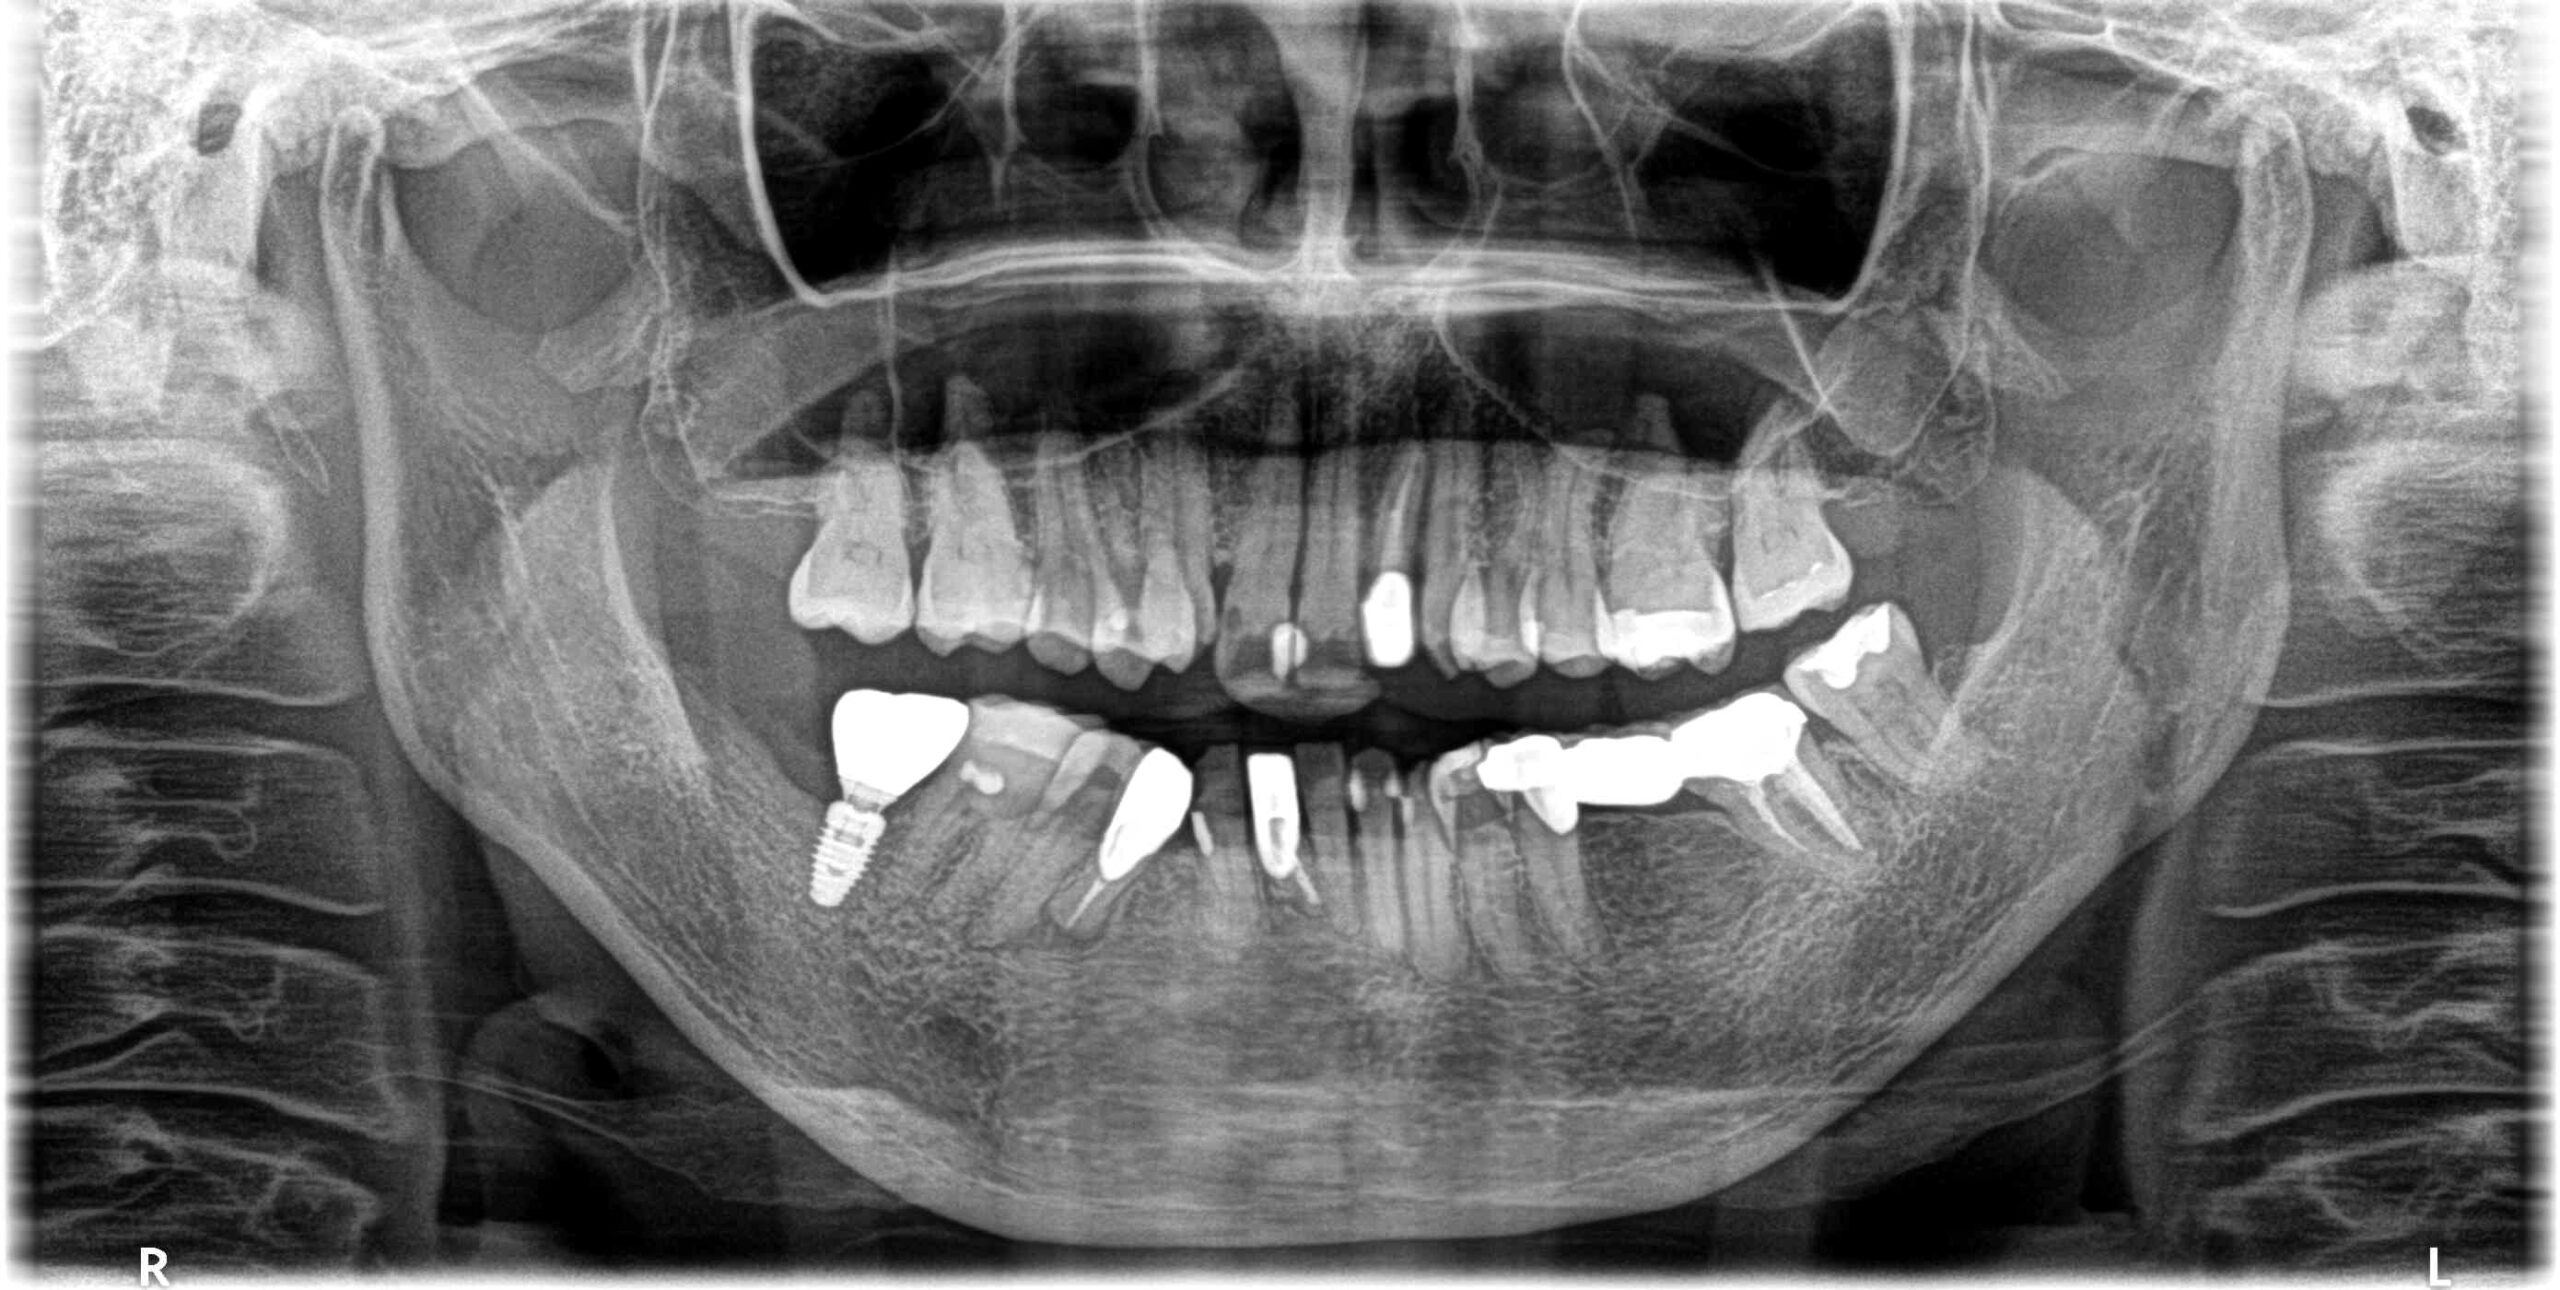

患者様は60代の女性で右下7番の歯が歯根破折で抜歯になり、抜歯後の欠損部にインプラント治療を行った症例です。

治療の流れとしては、静脈内麻酔下にて右下7番の欠損部の骨内に1本のスウェーデン製のノーベルバイオケア社のインプラント(フィクスチャー)を埋入して、ON1ベースアバットメント(土台)を装着して仮歯を経て最終上部構造(ジルコニアセラミック)をスクリュー固定しました。